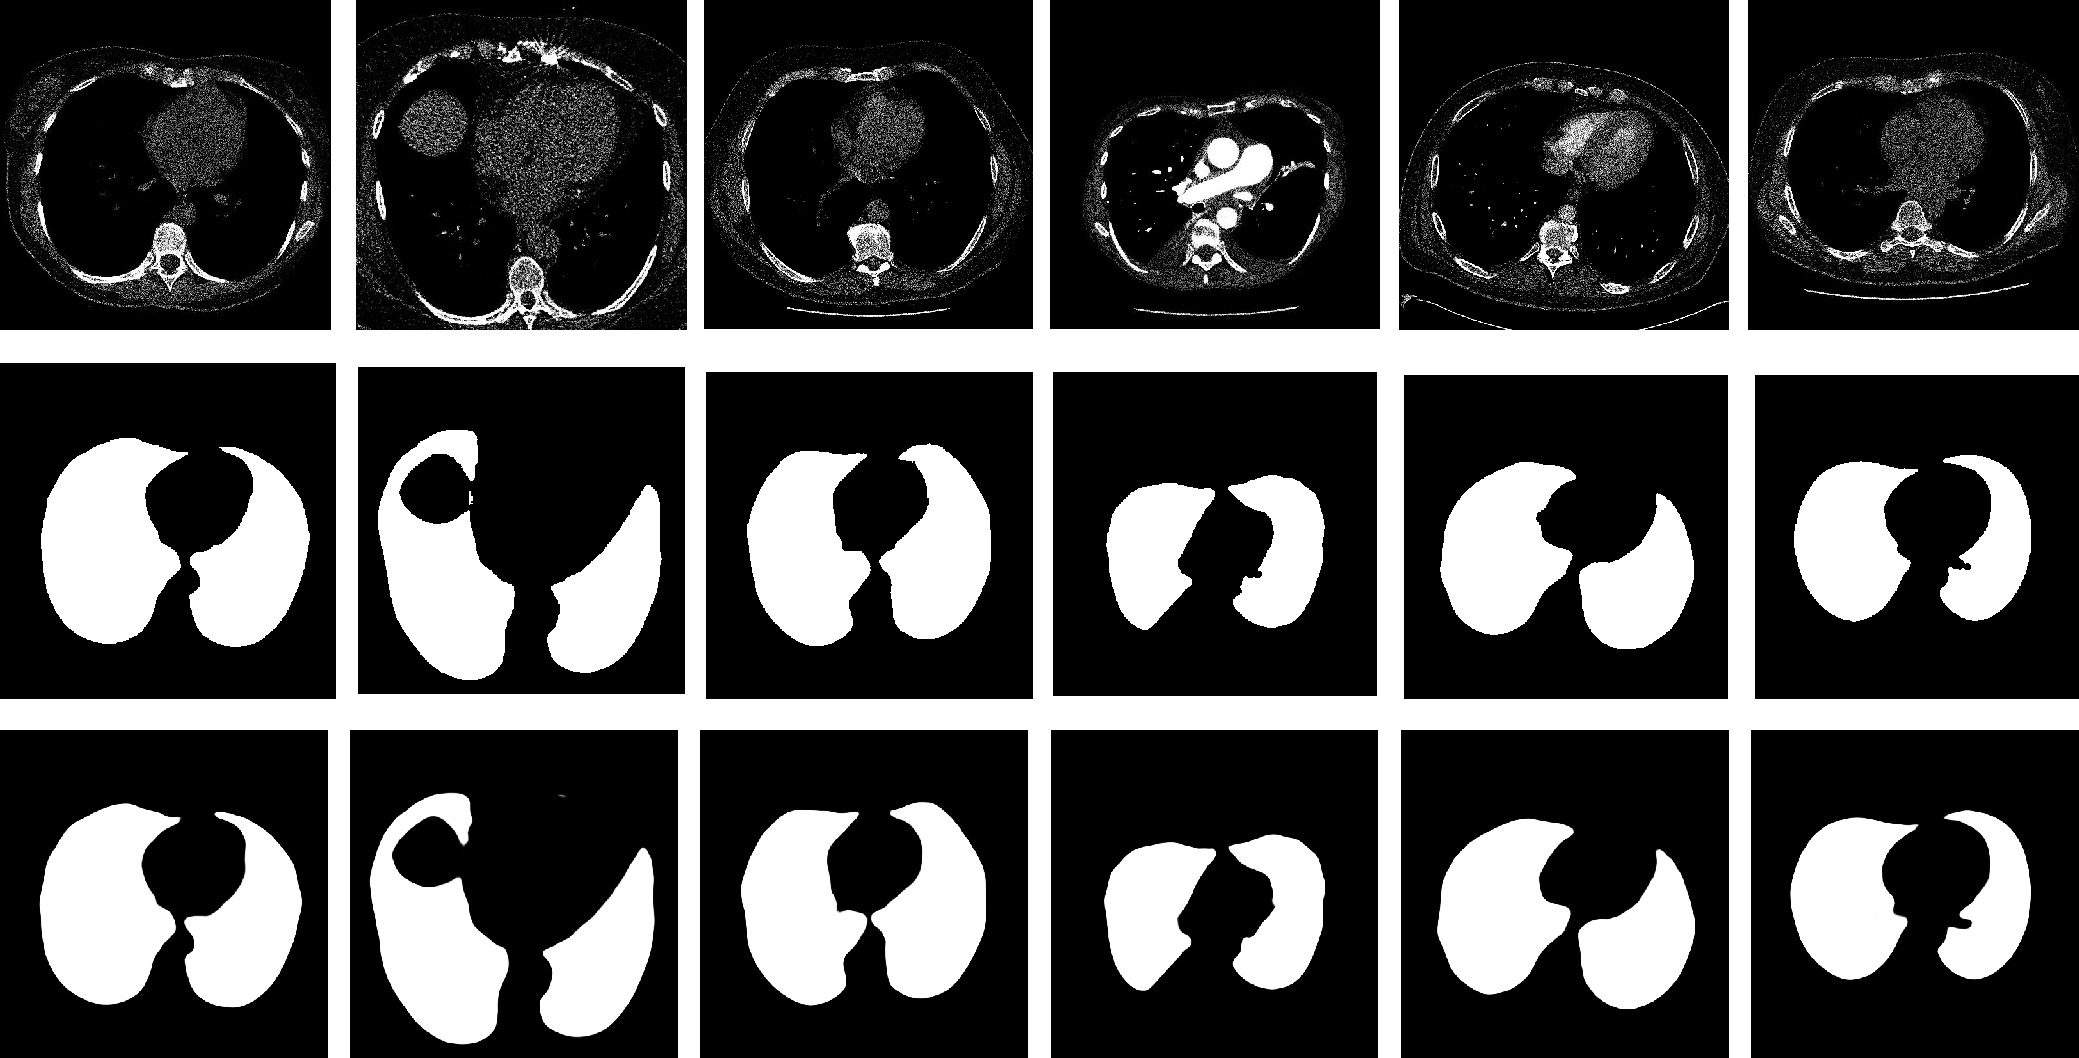

• Colorectal cancer has become a global public health concern. Removing polyps before they become malignant can effectively prevent the onset of colorectal cancer. Currently, multi-receptive field feature extraction and attention mechanisms have achieved significant success in polyp segmentation. However, how to effectively fuse these mechanisms and fully leverage their respective strengths remains an open problem. In this paper, we propose a polyp segmentation network, MFAINet. We design an attention-integrated multi-receptive field feature extraction module (AMFE), which uses layering and multiple weightings to fuse the multi-receptive field feature extraction and attention mechanisms, maximizing the extraction of both global and detailed information from the image. To ensure that the input to AMFE contains richer target feature information, we introduce a multi-layer progressive fusion module (MPF). MPF progressively merges features at each layer, fully integrating contextual information. Finally, we employ the selective fusion module (SFM) to combine the high-level features produced by AMFE, resulting in an accurate polyp segmentation map. To evaluate the learning and generalization capabilities of MFAINet, we conduct experiments on five widely-used public polyp datasets using four evaluation metrics. Notably, our model achieves the best results in nearly all cases.